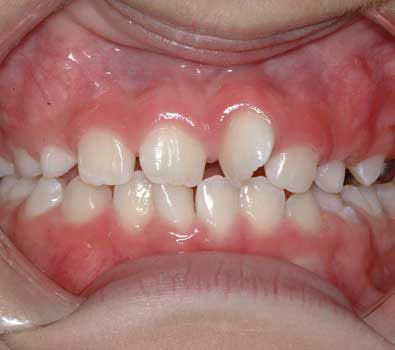

Gaps between childs teeth

It is normal and even "ideal" for baby teeth to have spacing between each other.

Keep in mind that when permanent teeth erupt, their size will be considerably larger than that of baby teeth. As the baby teeth are lost, the erupting permanent tooth will quickly take advantage of this excess space.

Children who do not have spacing in their primary dentition can have a higher incidence of crowding (crooked teeth) in the permanent dentition.